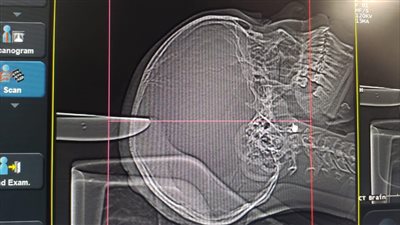

إجراء عملية دقيقة لاستئصال ورم كبير بالمخ بمجمع السويس الطبي

الرعاية الصحية: نجاح جراحة ميكروسكوبية دقيقة لاستئصال ورم عميق ببطينات المخ بمجمع الإسماعيلية الطبي